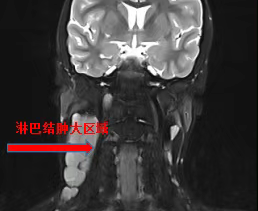

8岁男孩小张在5个月前发现无明显诱因的右侧颈部无痛性包块逐渐变大,包块生长速度快、呈多发性,辗转多家医院就诊未好转,收住市一院儿外科完善术前检查后,初步诊断为淋巴瘤,决定手术治疗。术中发现肿瘤大且多发,较大者约9x5cm,深达颈椎,与颈纵紧密粘连,神经血管已经失去正常的解剖结构,手术医师仔细分离周围血管神经,逐一结扎分支血管后,完成切除多个淋巴瘤,手术耗时1小时30分钟,术后病检结果显示:典型霍奇金淋巴瘤。霍奇金淋巴瘤(Hodgkinslymphoma,HL)又称霍奇金病,是青年人中最常见的恶性肿瘤之一。